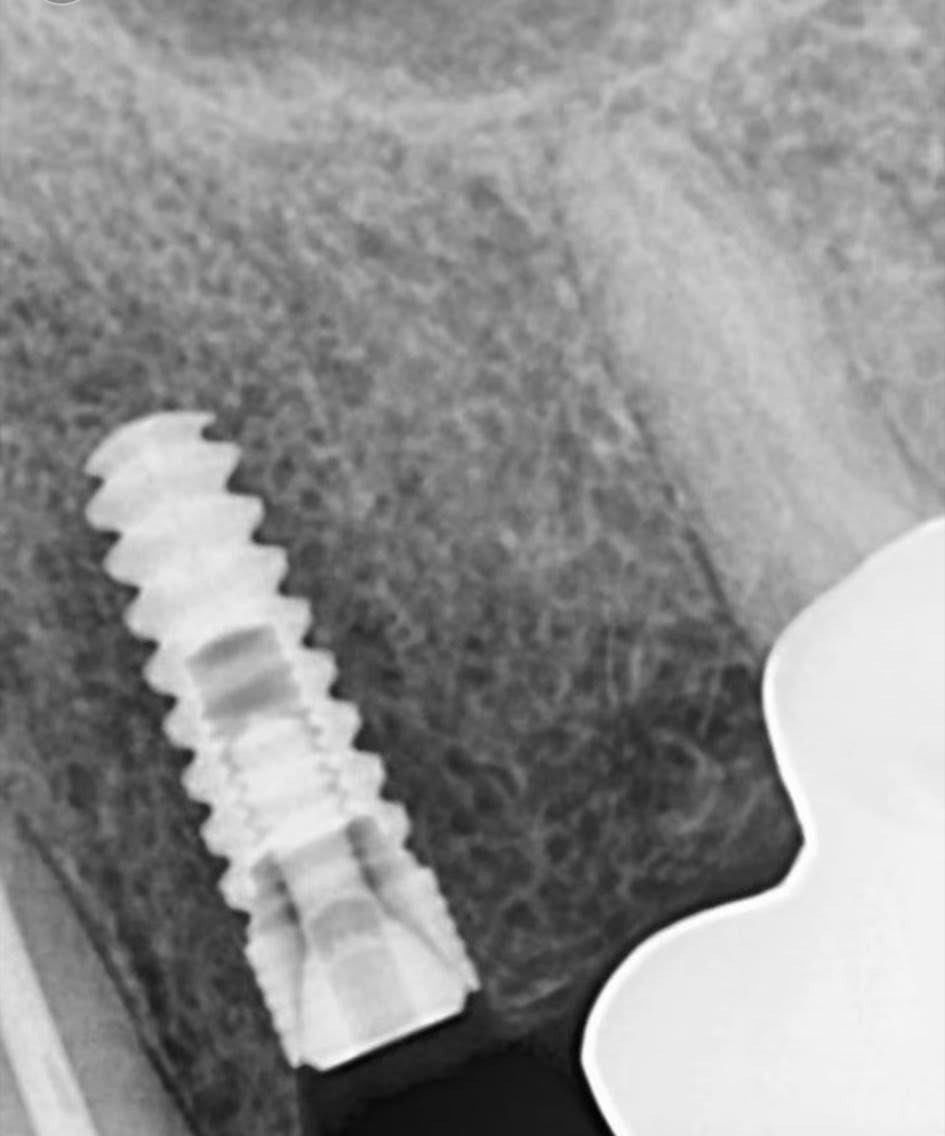

د. محمد مطيع - زراعة TB Implants لحالة فقدان أسنان معقدة

د. محمد مطيع - زراعة TB Implants في الفك السفلي الأيسر لتعويض فقدان الأسنان مع زراعة فورية.